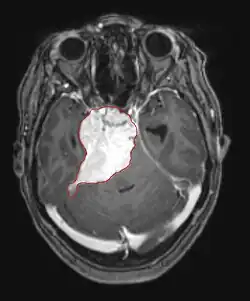

Hirnmetastasen sind die häufigsten intrakraniellen Neoplasien bei Erwachsenen, die zehnmal häufiger vorkommen als primäre Hirntumoren. Sie treten bei 20 bis 40 Prozent der krebskranken Erwachsenen auf und sind hauptsächlich mit Lungen- und Brustkrebs sowie Melanomen assoziiert. Diese Läsionen sind das Ergebnis der Ausbreitung von Krebszellen durch den Blutkreislauf und treten am häufigsten an der Verbindung der grauen mit der weißen Substanz auf, wo sich der Querschnitt der Blutgefäße ändert und damit Tumorzellembolien eingeschlossen werden. 80 Prozent der Läsionen treten in den Gehirnhälften auf, 15 Prozent im Kleinhirn und 5 Prozent im Hirnstamm. Ungefähr 80 Prozent der Patienten haben eine Anamnese von systemischem Krebs und 70 Prozent haben multiple Hirnmetastasen.

Bei Diagnose und Behandlung dieser Läsionen wurden in jüngster Zeit erhebliche Fortschritte erzielt, wodurch das Überleben und die Kontrolle der Symptomatik verbessert wurden. Das Auftreten von Anzeichen und Symptomen ähnelt denen anderer massiver Läsionen im Gehirn. Das Diagnoseverfahren der Wahl ist die Kernspintomographie unter Verwendung von Kontrastmitteln.

Die Literatur zeigt äquivalente Ergebnisse für Chirurgie und Radiochirurgie. Letzteres scheint bequemer, effektiver und sicherer für kleine Läsionen oder in Regionen zu sein, die für eine Operation nicht zugänglich sind. Die Radiochirurgie ist eine sinnvolle Alternative für Patienten, die aus medizinischen Gründen nicht operiert werden können. Die Operation ist jedoch eindeutig die optimale Methode, um Gewebe für die Diagnose zu erhalten und die Läsionen zu entfernen, die einen Masseneffekt verursachen. Daher sollten Radiochirurgie und Chirurgie besser als zwei komplementäre, aber unterschiedliche Methoden betrachtet werden, die je nach der unterschiedlichen Situation des Patienten angewendet werden.[44] Für fast 50 Prozent der Patienten mit einem oder zwei Hirnmetastasen kommt eine chirurgische Entfernung aufgrund der Unzugänglichkeit der Läsionen, der Ausdehnung der systemischen Erkrankung oder anderer Faktoren nicht in Frage. Diesen und anderen Patienten mit multiplen Metastasen wird normalerweise eine panenzephale Strahlentherapie als Standardbehandlung angeboten. Tatsächlich erreichen bis zu fast 50 Prozent von ihnen mit dieser Therapie eine Verbesserung der neurologischen Symptome und 50 bis 70 Prozent eine erkennbare Reaktion.[45][46][47] Bei Hirnmetastasen wird die Chemotherapie selten primär angewendet.